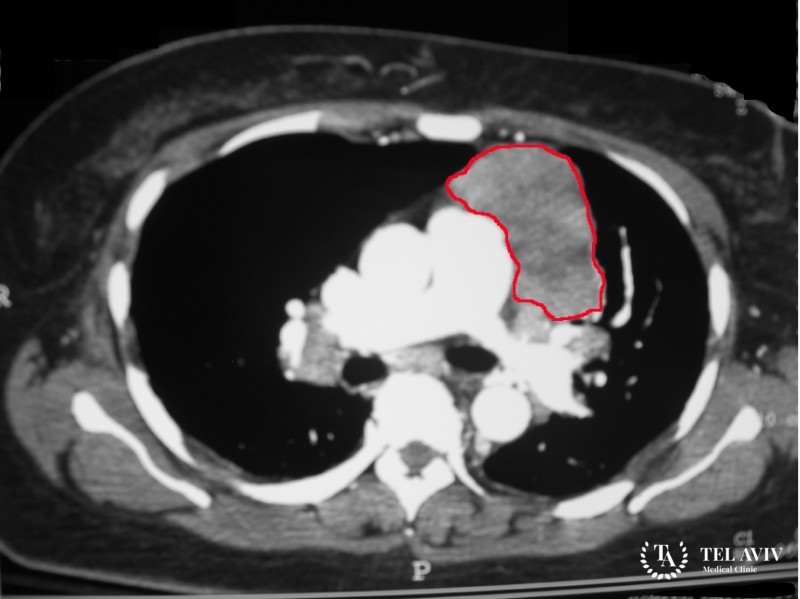

Тератома – является образованием, которое содержит элементы всех трех зародышевых листков. Данная патология встречается крайне редко и болеют им в основном женщины. Опухоль имеет грушевидную форму и может достигать до 15 см в диаметре. В медицине известны случаи, когда доброкачественное образование с течением времени перерождалось в злокачественное. Поэтому врач, который обнаружил патологию приступает к немедленному ее лечению.

- Рентгенография;

- Эхо-КГ;